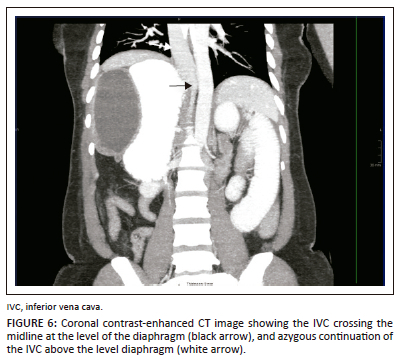

The chest CT demonstrated a left-sided inferior vena cava (IVC) within the abdomen. Above the diaphragm, the IVC crossed the midline and continued into the chest as the azygous vein. There was no hepatic IVC (Figure 6). There was a common origin of the left common carotid artery and brachiocephalic trunk, in keeping with a Bovine aortic arch. The right lung was trilobed with an eparterial bronchus. The left lung was bilobed with a hyparterial bronchus.

Abnormal cardiac position is more common in right isomerism than left isomerism. Mesocardia or dextrocardia occur in 40% - 50% of patients with left isomerism.2 Azygous continuation of the IVC is commonly found in left isomerism, whereas bilateral superior vena cava (SVC) may occur in both left and right isomerism.4 Partial anomalous pulmonary venous connection can occur in left isomerism, while total anomalous pulmonary venous connection occurs commonly in right isomerism. Atrial septal defects (ASD) and atrioventricular septal defects (AVSD) are more common in right isomerism than left isomerism.2 The presented patient had levocardia, azygous continuation of the IVC, no anomalous pulmonary venous connections and no ASD or AVSD.